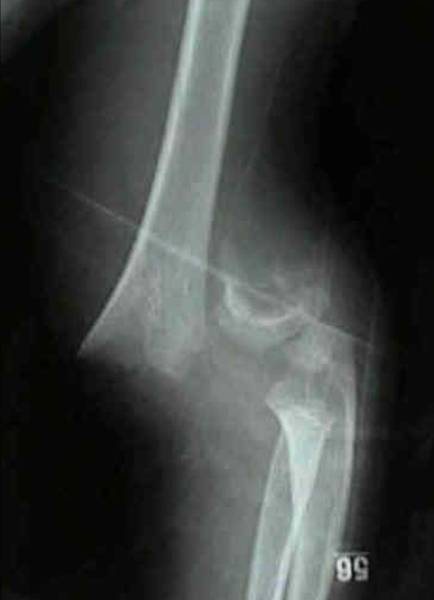

| Imaging |

- Radiographs

- recommended views

- AP and lateral x-ray of the elbow (really of the distal humerus)

- findings

- posterior fat pad sign

- lucency on a lateral view along the posterior distal humerus and olecranon fossa is highly suggestive of occult fracture around the elbow

- measurement

- displacement of the anterior humeral line

- anterior humeral line should intersect the middle third of the capitellum in children > 5 years old, and touches the capitellum in children in children <5.

- capitellum moves posteriorly to this reference line in extension type fractures and anteriorly in flexion type fractures

- alteration of Baumann angle

- Baumann's angle is created by drawing a line parallel to the longitudinal axis of the humeral shaft and a line along the lateral condylar physis as viewed on the AP image

- normal is 70-75°, but best judge is a comparison of the contralateral side

- deviation of >5-10° indicates coronal plane deformity and should not be accepted